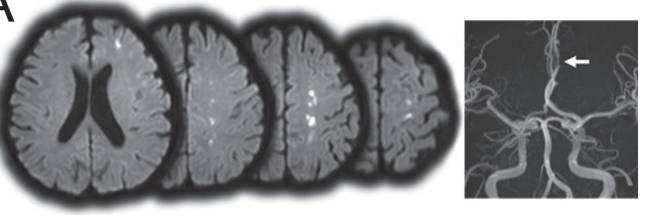

图5 DWI提示皮层多发梗死灶。MRA可以发现左侧A2-A3交界处明显狭窄。